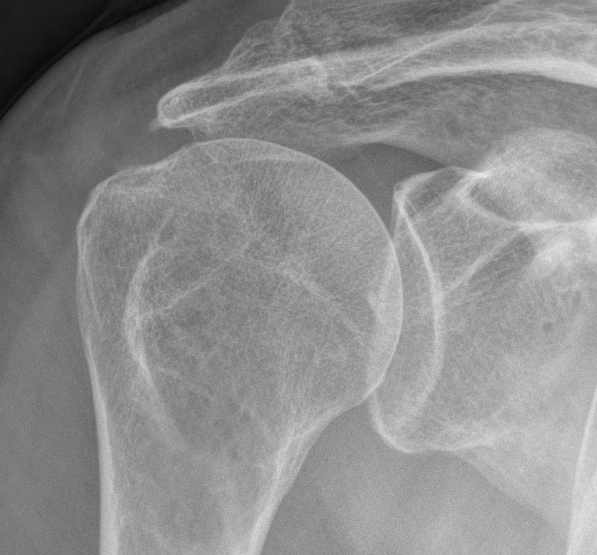

Xray

Superior migration of head without arthropathy